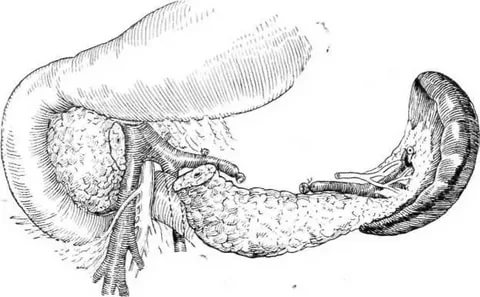

УЗИ диагностика кольцевидной поджелудочной железы: что важно знать